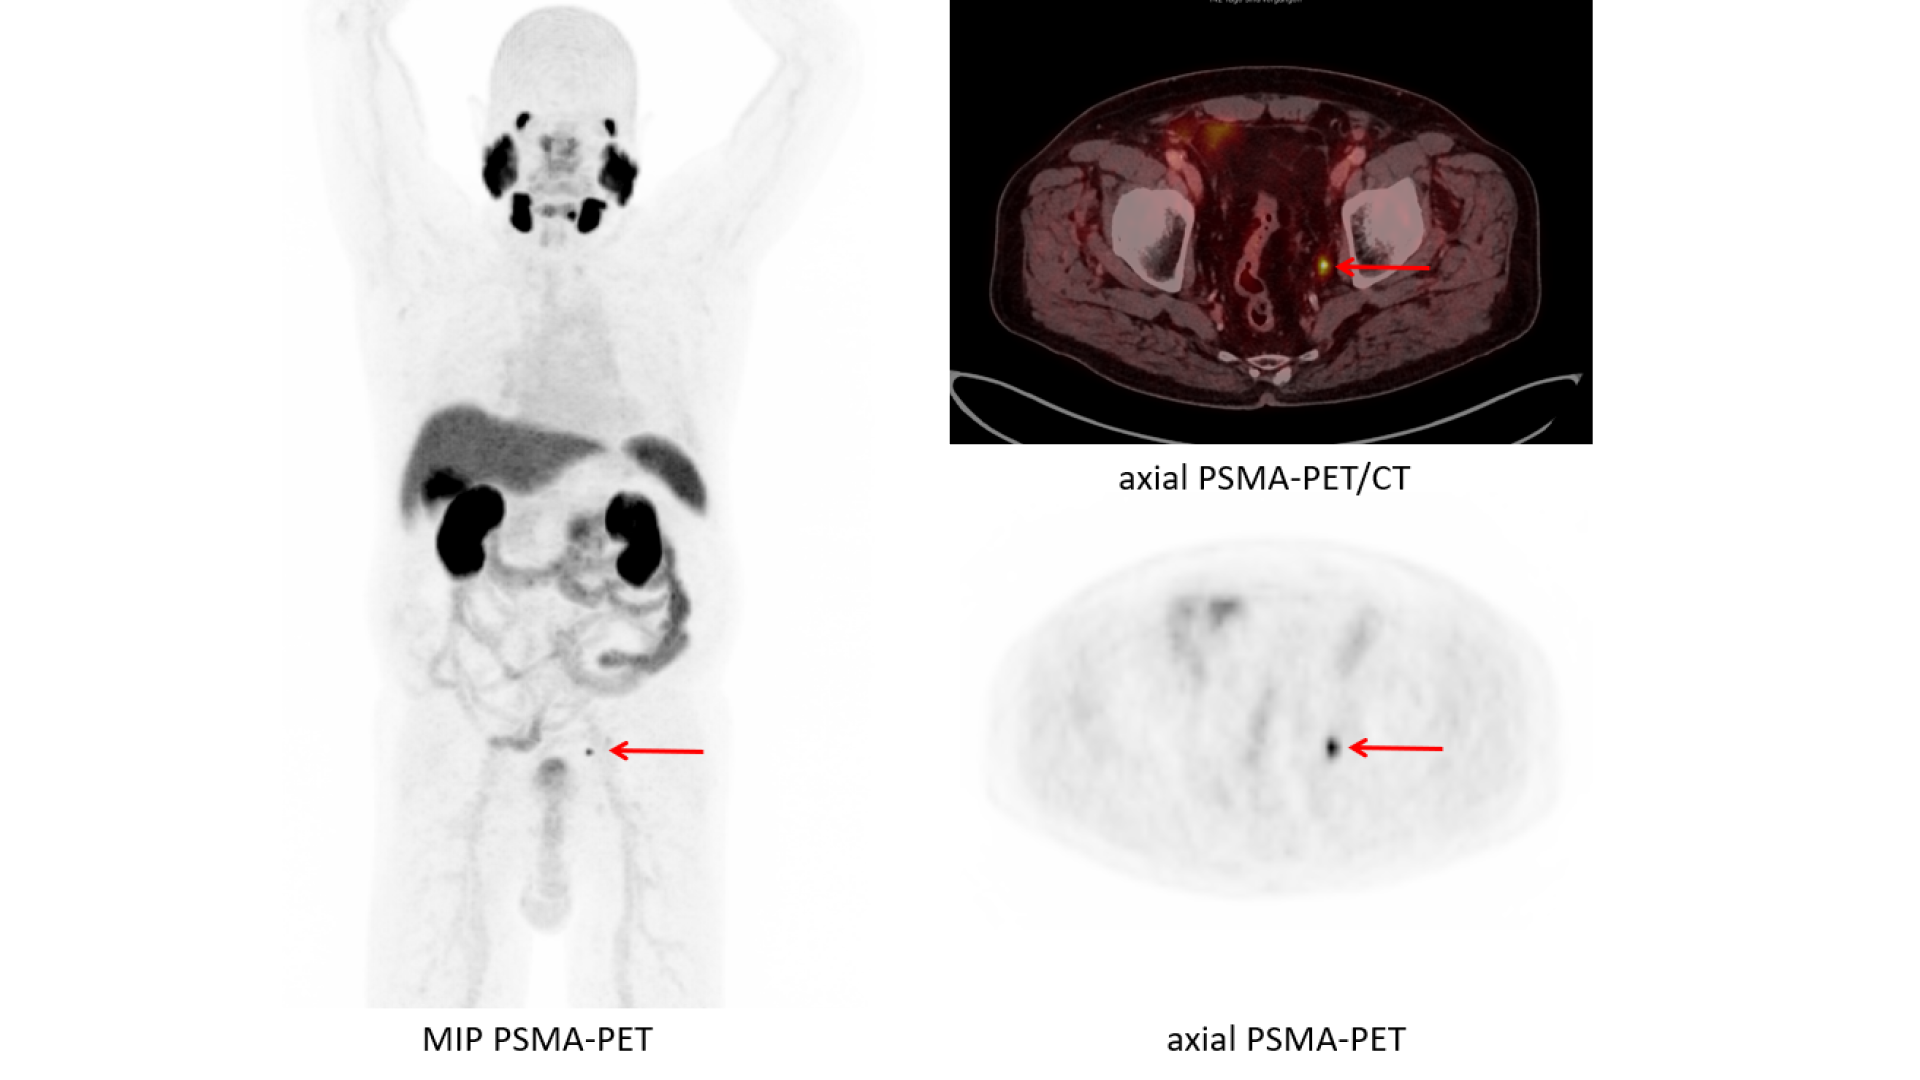

Пэт псма что это

Пэт псма что это 104 фотографий